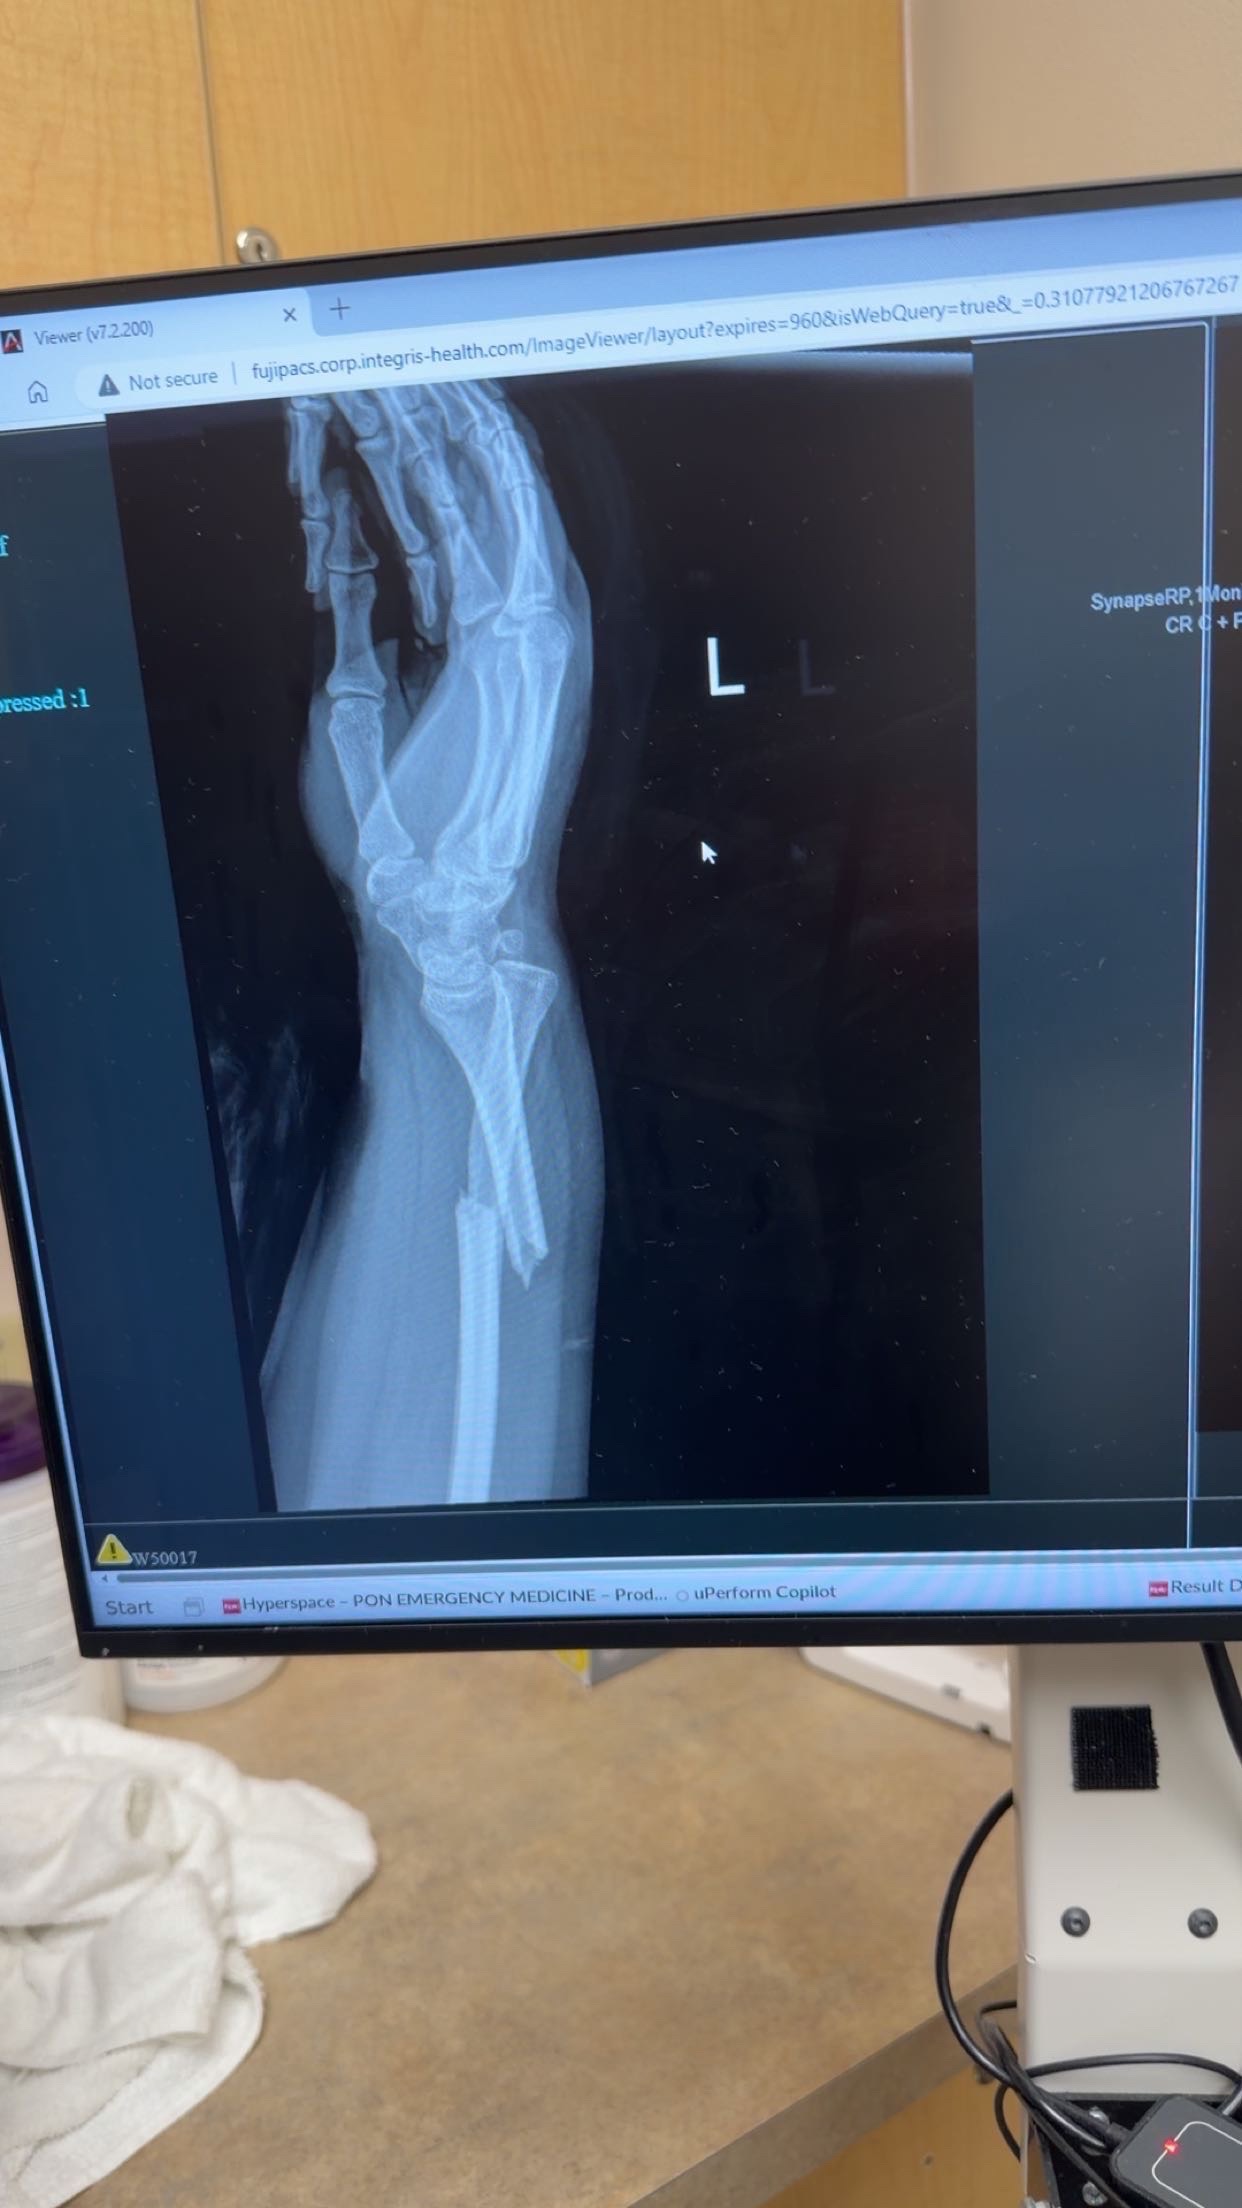

My name is Jessica Montes. I’m a 21 year old mother of a 1 year old little girl, Jena. I reside in Ponca City, Oklahoma with my daughter and my fiance Chase. I am unfortunately having to make this GoFundMe because on Monday, March 23rd, 2026 at 5:19pm- my whole world was turned upside down in a matter of seconds. I was involved in a terrible car accident on my back to Ponca from work in Tonkawa Oklahoma, on US Highway 60. Which has ultimately cost me my car, my arm and wrist/hand, my ability to go back to work for many weeks due to healing, and the ability to take care of my own small daughter on my own. From this accident, I have a broken arm(which I just had surgery for this morning), fractured wrist, many severe burns from the seatbelt that saved my life, and lots of severe bruising and cuts and strains. I’m in a huge amount of endless pain. I’m trying to be in good spirits but my car is going to be totaled and my fiances Tahoe broke down today on the way to get our daughter. I’m out of work, and my fiance is having to take care of our daughter, take care of me, work long hours during the day, find a babysitter for our daughter during that time and now has the burden of our now only vehicle breaking down. They say when it rains, it pours and right now I’m feeling that wrath. We are now trying to keep our heads above water while battling my recovery process, insurance claims, being car-less, on top of our normal life bills and expenses. I’m very thankful and blessed to be alive but I did not ask for this to happen to me. Accidents happen, and I’m grateful everyone involved is okay, but I was doing everything right and in a split second, my life was almost taken from me and now we’re left picking up the pieces. If anybody can find it in their hearts to help us through this very tough time, it would be greatly appreciated beyond words could express! I’m not the type of person to ever ask people for help. I have a great work ethic and love my job at Mediclaims Inc in Tonkawa and I work really hard for the things I have in my life and also for my babygirl. My parents always taught me to never rely on anyone else and it hurts me to even have to ask for help. Please do not feel like you have to donate but we would like to ask if you would share my story and help me get this out there. I appreciate all the generous love and support I have recieved from my family and friends and community. Thank you all so much for taking your time to read/share and donate.